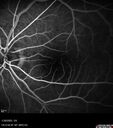

83 year old man Retired aerospace engineer. Blurred vision in both eyes with complex eye history. No acute changes noted by patient. Prior macula-on retinal detachment repair in the right eye a year ago (buckle, vitrectomy, laser, gas, ST Kenalog). Medical Hx: Hypertension, Systemic. Hyperlipidemia. Asthma. Surgical Hx: left shoulder ac separation 2013. Turp 2010. Systemic Meds: Lisinopril, 10 mg oral tablet bid. simvastatin QD. muscinex DM QD. Metformin 100 MG QD. Allergy Medicine. HCTZ QD. PRILOSEC QD. MYBETRIC. MONTULAKAST. Aspirin 81 mg. QUETISPINE 150 MG QD. ESATATOPRAM 20 MG QD. VA OD: Dcc20/50 VA OS: Dcc20/50-2 IOP: TP: OD:15 OS:16 Converted to wet AMD after a single Izervay Treatment

Conversion to Wet AMD after Izervay28 views83 year old man whose left eye had minimal GA and converted from dry to wet AMD after a single Izervay treatment00000